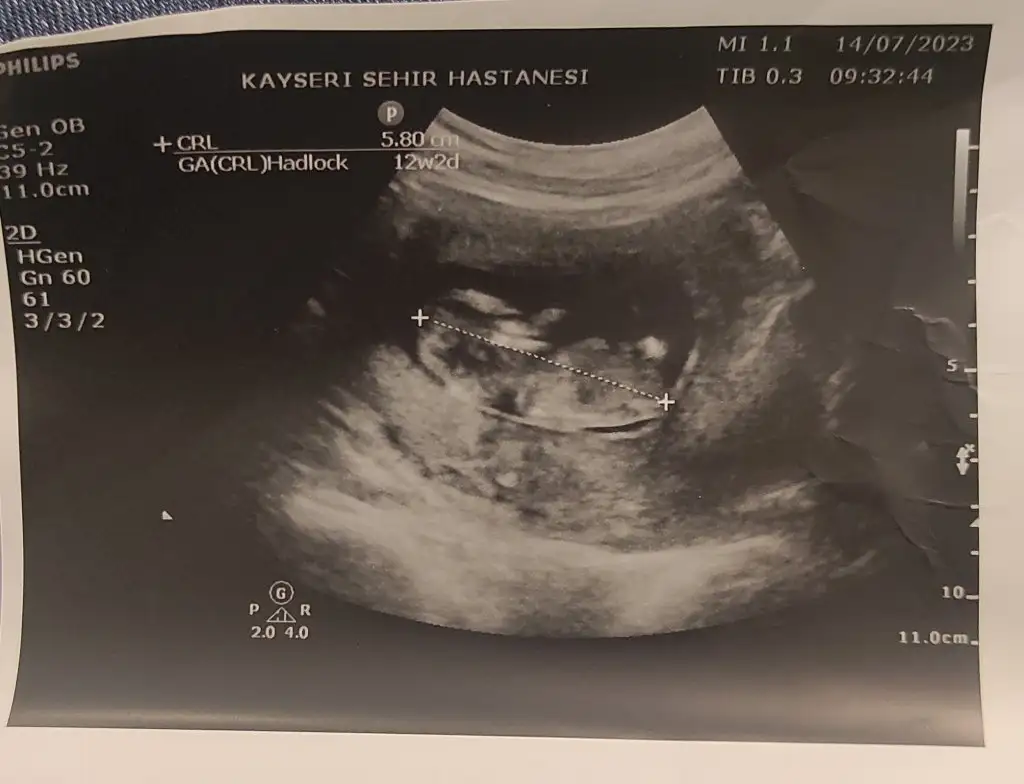

Kizçeler cinsiyet tahmin edebilirmisiniz 🤩

AnlatilmazYasanir AnlatilmazYasanir canım senden özellikle istiyorum🤗

IMG_20230714_104058.webp

yaa ne kadar güzel maşallah, bende yarın doktora gideicem 12+2 deyiz bi tahminde bulunur heralde başından beri erkek hissediyorum ama rüyamda da kız gördüm bakalım ne olucak insan bi an önce öğrenmek istiyor birde kız arkadaşlarım tembihledi parti yapıcaklar yarın beli olsada öğrenemicez yani